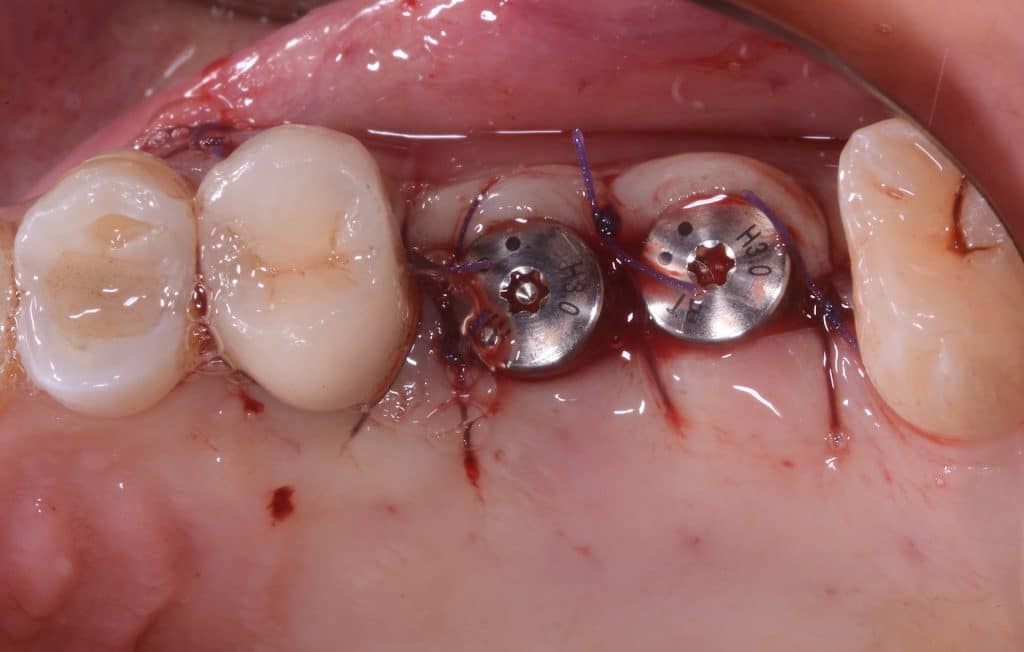

- Two 8 mm Straumann TLX implants placed

- TLX implants have an excellent primary stability in most cases (as post-extraction cases). But in the case of sinus lift they tend to lose primary stability in the last stages of screwing. Therefore in this case a conical implant is preferable.

- Implants can be seen inside the maxillary sinus through the bone window

occlusal view, implants placed